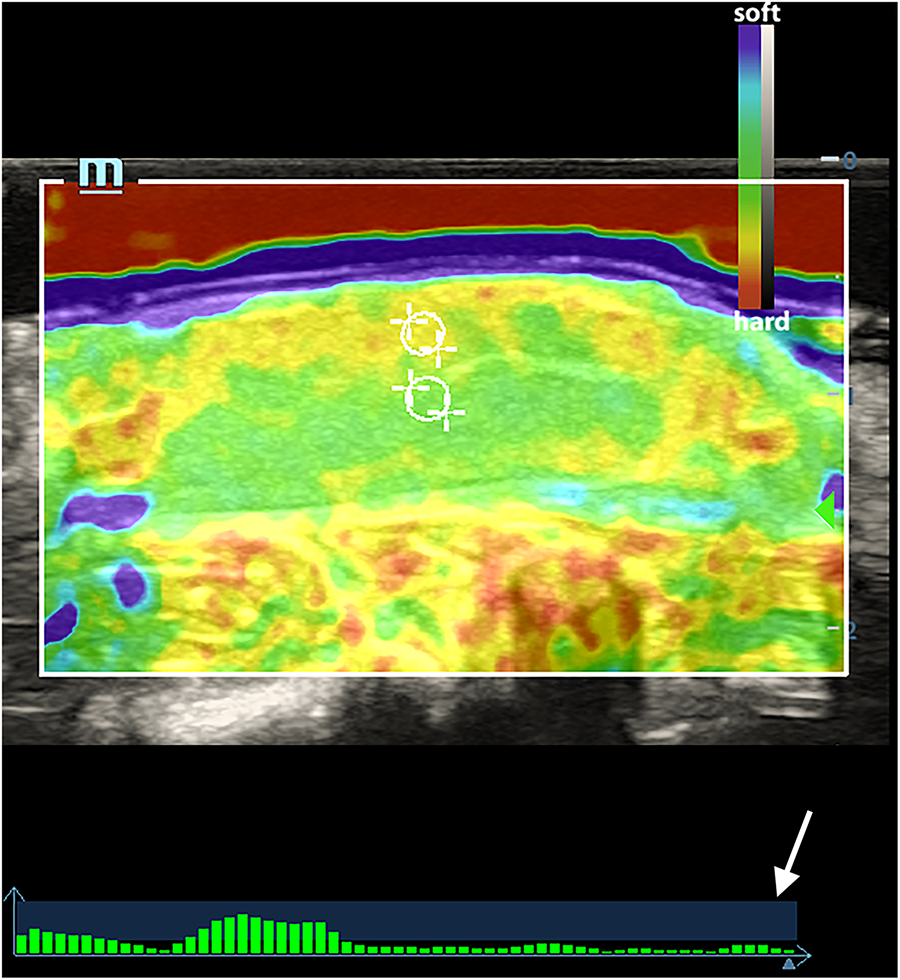

The elastography examinations were conducted by a sonographer with more than 8 years of experience in clinical ultrasound diagnosis and at least 5 years of experience in UE. An M9cv ultrasound system (Mindray Medical Solutions, Shenzhen, China) equipped with an elastography-compatible L12–4s transducer (frequency range of 4–12 MHz) was utilized for the stiffness assessment both pre- and post-operation. The ultrasound gel pad was placed on the surface of the testicles. The elastograms were obtained in the largest longitudinal section and the elasticity acquisition box was placed in the middle of the elastogram, including the whole testicle. Local strain was provided by the operator with manual compressions using the ultrasound transducer. A quality feedback bar was used to control the maintenance of the applied force at the bottom of the screen. The bars on the vertical axis in the blue area indicated the optimal compression. Elastography enables users to obtain tissue elasticity distribution details from intuitive images by providing 2D color imaging of tissue stiffness information. In the color-coded map, the hard tissues appear in red, soft tissues in blue to purple, and intermediate degrees of elasticity in green and yellow (Figure 1).

Figure 1

An elasticity map of a normal testicle. The white circles indicated the ROI of the testicular parenchyma beneath the capsule and in the central area. The white arrow indicates the quality feedback bar.

As shown in Figure 1, normal testicle parenchyma is predominantly green and blue in SE, with the skin and capsule area in yellow. After 360° and 720° TT, the central and border areas of the parenchyma in the twisted testicles were an uneven yellow or yellow-red color. Some of the twisted cases were red in color with a “stiff ring sign” in the capsule area. The SE scores in different groups at various times are shown in Table 1.